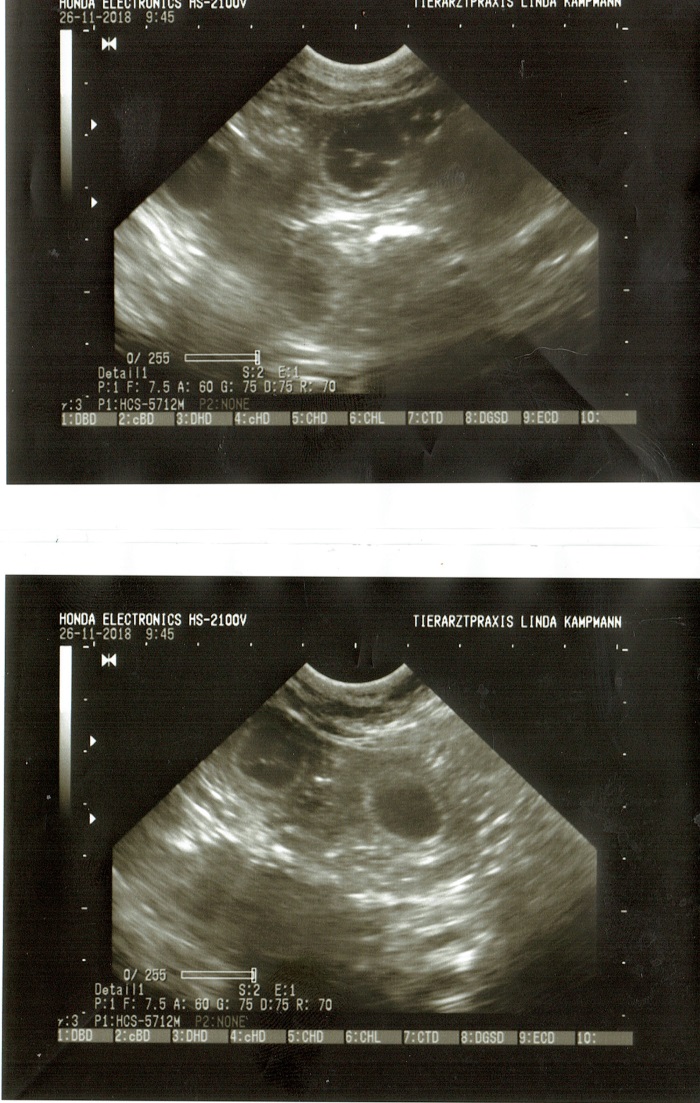

Wir schreiben heute den 26.11.2018

Heute ist der 26. Tag nach dem Decken durch Curry. Heute Morgen waren mir zum Ultraschall bei unserer lieben Tierärztin Linda Kampmann. Kensi wollte nicht so recht das Geheimnis selber lüften.

Nachdem Ultraschall steht nun aber fest, das Kensilienchen trächtig ist. Linda konnte deutliche Fruchtanlagen sehen. Wir sind super happy und erwarten eine spannende Zeit.

Das Startgewicht liegt bei 31,8kg und der Bauchumfang beträgt 66cm.

Ab den 23. Tag kann die Trächtigkeit mit dem Ultraschall nachgewiesen werden. Milchiger, teilweise zähflüssiger Schleim kann abgesondert werden.